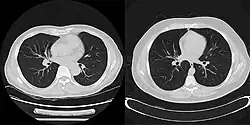

Here is an example that illustrates the benefits of iterative image reconstruction for cardiac MRI.[21]